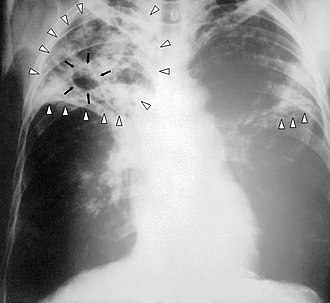

Klasični simptomi aktivne TBC infekcije su kronični kašalj s hemoptizom (krvavi iskašljaj), vrućicom, noćnim znojenjem i mršavljenjem. (TBC se naziva i “sušicom” jer bolesnici gube tjelesnu masu, kao da se suše.) Infekcija drugih organa izaziva niz različitih simptoma. Medicinska dijagnoza aktivne TBC postavlja se na osnovi radiološkog nalaza (obično rentgenske slike pluća), mikroskopske pretrage tjelesnih tekućina i mikrobiološkog uzgoja uzročnika u kulturi. Dijagnoza latentne TBC se zasniva na Mantouxovom testu i pretragama krvi. Liječenje tuberkuloze nije jednostavno, i sastoji se od dugotrajne primjene brojnih antibiotika. Osobe s kojima bolesnik dolazi u dodir također se podvrgavaju probiru i ako je to potrebno, liječenju. U slučajevima tuberkuloze otporne na više lijekova sve veći problem predstavlja otpornost na antibiotike. Kako bi se TBC spriječila, treba provoditi probir stanovništva na bolest i cijepljenje s bacilom Calmette–Guérin (BCG) cjepivom.

Dijagnozu aktivne tuberkuloze je samo na osnovi znakova i simptoma teško postaviti.[52] Dijagnozu je teško postaviti i u osoba s imunosupresijom.[53] Međutim, osobe sa znakovima bolesti pluća ili s općim simptomima trajanja duljeg od dva tjedna mogle bi bolovati od TBC.[53] Tipične početne pretrage su rendgen prsišta i višestruko nasađivanje sputuma na mikrobiološke hranjive podloge za uzgoj acidorezistentnih bacila.[53] U zemljama u razvoju se ne izvode interferon-γ release assays (IGRAs) niti tuberkulinski kožni test.[54][55] U osoba zaraženih HIV-om IGRAs ima slična ograničenja.[56][57]